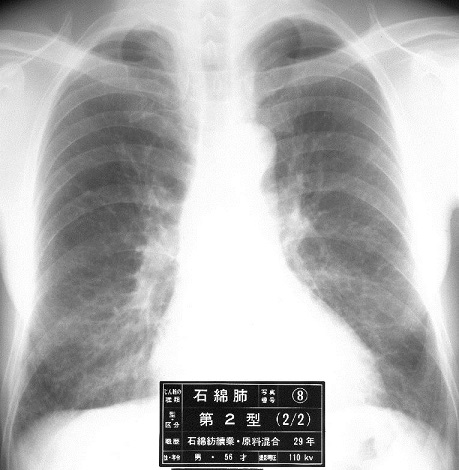

一方石綿肺は下肺野優位の不整型陰影が出現する。

石綿肺Asbestosis:石綿粉じんを吸入することによって肺に生じた線維増殖性変化を主体とする疾病=石綿粉じんによる肺線維症+気道の慢性炎症

・下肺野優位の不整型陰影

・診断は胸部X線写真による

下肺野優位の不整型陰影を「じん肺標準エックス線写真」と比較して判定することになる。

0型(-/1、0/0、0/1):PR0

1型(1/0、1/1、1/2):PR1

2型(2/1、2/2、2/3):PR2

3型(3/2、3/3、3/+):PR3

の12通りの診断となり、Ⅰ刑以上の所見がある場合、石綿肺と診断することになる。